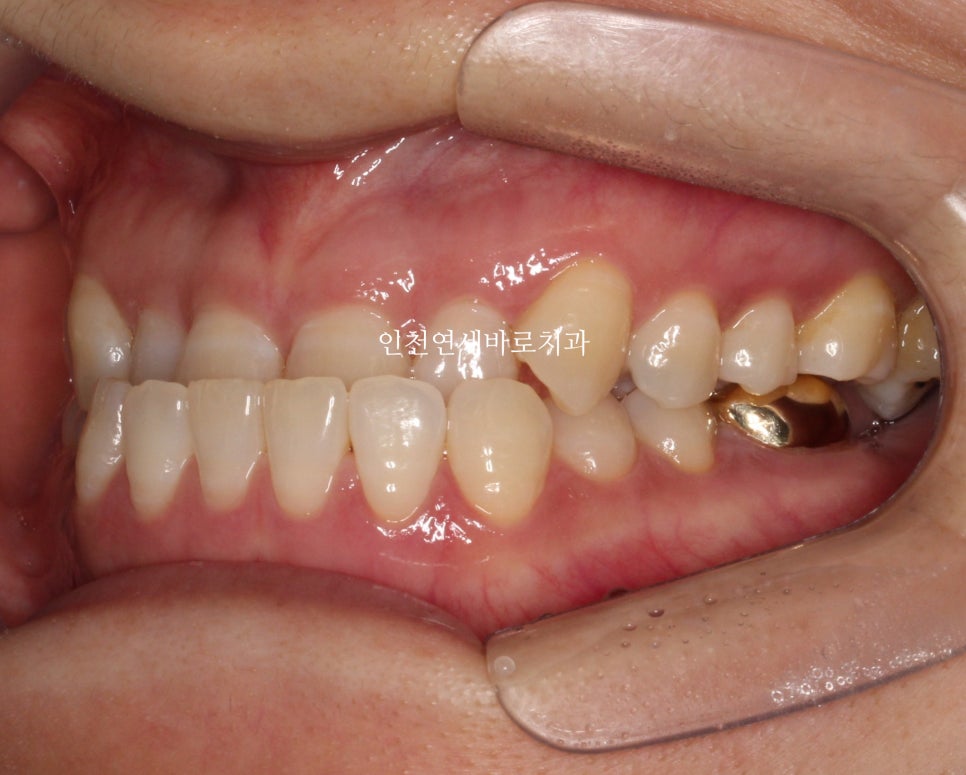

처음 오셨을 때 사진

치료를 할때 앞니를 넘기는 과정이 제일 힘들답니다.